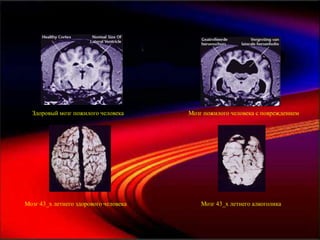

Темный шоколад и мозг

Здоровый мозг пожилого человека                 Мозг пожилого человека с повреждением

Мозг 43_х летнего здорового человека                   Мозг 43_х летнего алкоголика